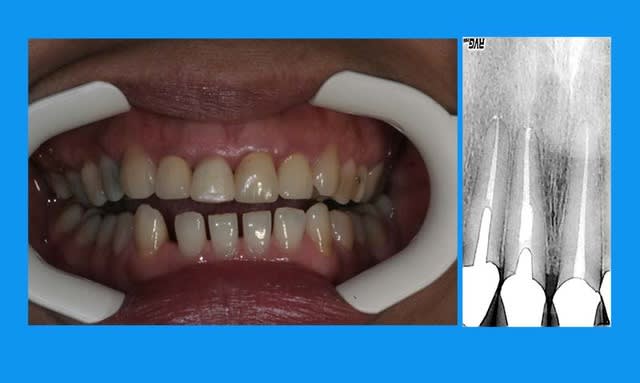

11 a du en passer par l'odf

non la patiente détestait ses diastèmes inf(microdontie relative des inc)

traction en 3 mois

normalement la contention doit être laissée en place 3 mois minimum

cela dit ds ce cas,un ttt odf pr les incisives du bas ayant été entrepris,elle est restée plus longtemps

pr repondre à noa... ce n'est pas moi qui fais l'odf,je me suis contentée de demander,puis de travailler en parrallèle et de concert